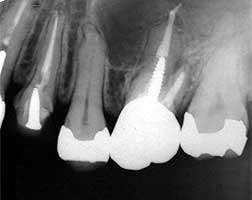

現在家の近くの歯科にかれこれ1年通院しています。それまでは、上の歯は右の12

が差し歯で456は神経はなしで、左の36も神経を抜いていて、下の歯は右は56神

経なし左は567がブリッジです。上の歯の456の歯茎が時々腫れたり膿がぽつぽつ

でたりしたのと、右下の6がたまにズキズキするので受診しました。

次に右上の4を治療中、膿が出たので5も掃除したら歯の根っこが割れていたので抜

歯しました。その時歯茎を上にあげる手術もしました。その時6の歯にも膿が見えてこ

の歯も△だそうです。しかもこの歯の根っこには神経をとるときの金属が折れて残って

いるとのことでした。5を抜歯した頃、また左上の456に膿がポツポツ出たので伝え

たところ456の掃除はしたので歯茎を見るとの事で切開しました。そしたら67の歯

の間に小指の先位の大きさに膿がたまっていたそうです。これで治らなければ、抜歯と

言われたのですが先日またポツッと膿が見えました。現在はこういう状況です。